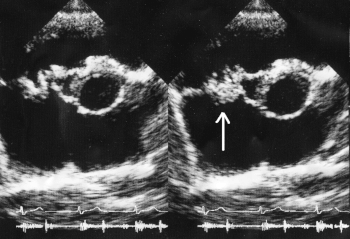

| A mitral valve vegetation caused by bacterial endocarditis | |